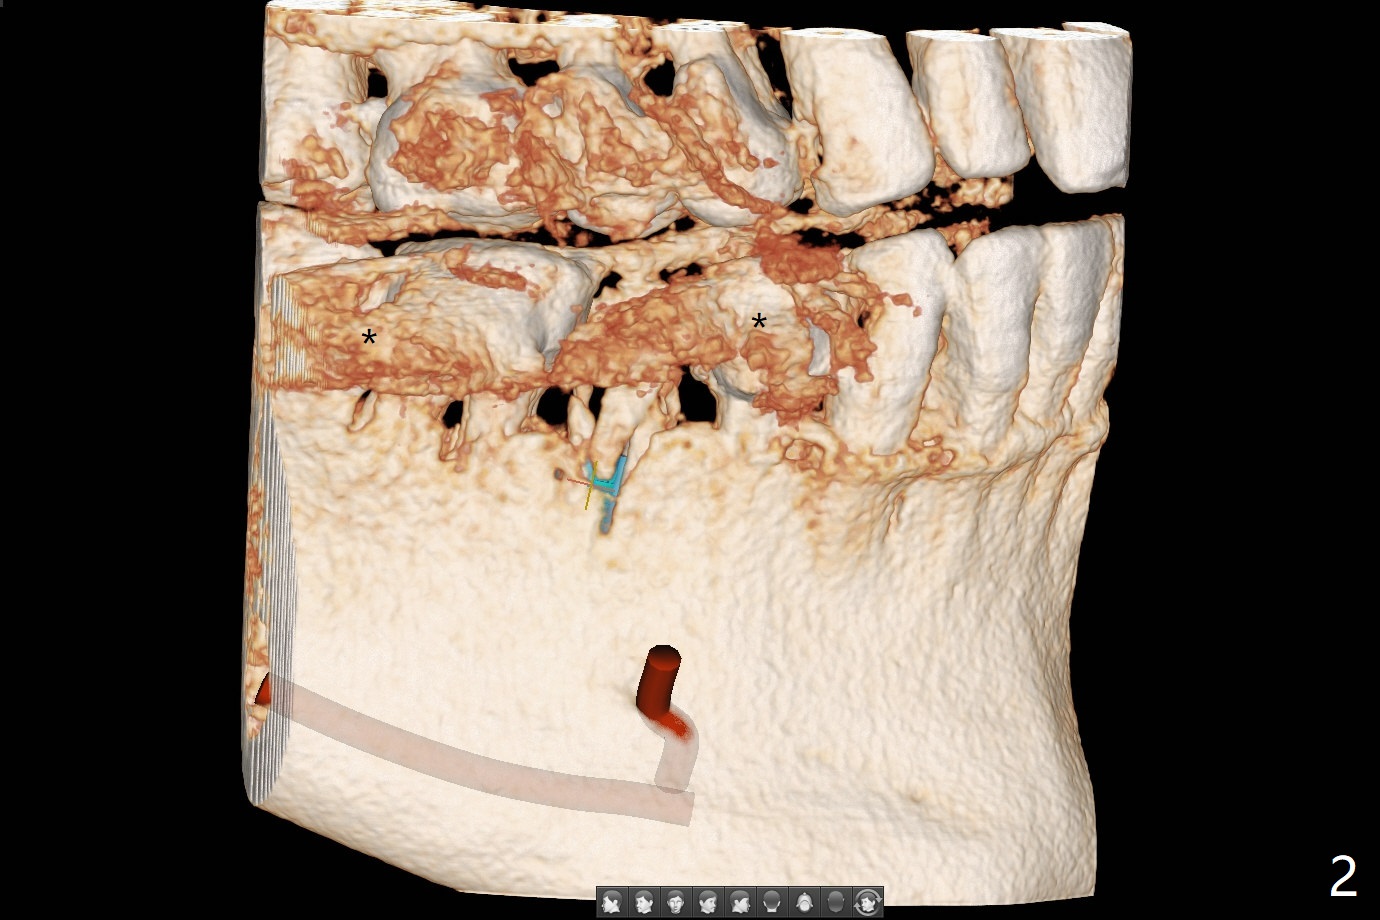

今天遇见一位特殊病人,54岁女,“右下一个牙齿断裂,我觉得一定要拔 (图一:5)。能不能同时种牙,减少痛苦。不过你是医生,一切由你决定”。为了炫耀,介绍导板,她还没有提钱的问题,估计必须再等十年才能碰见怎么有远见的土豪(夸张)。所以我们迫不及待拍摄CT,然后取模。至今有没有不对的地方,尤其是拍摄CT。要做导板周围(前后)有牙冠,在拍摄CT下,会产生折射(图二:*),影响CT精确度,不能与口内模型互相融合,从而影响导板精确度。如果实在想做导板,必须事先在牙冠上制作树脂cone(图三:红色三角形),然后拍摄CT和取模(或者scan),实验员才能准确融合两个图像。对于这个病例,只能做徒手种植,减少射线。不过增加手术时间,为了不损伤颏神经(图四),可能需要多次拍摄根尖片,增加无限的烦恼,一失足成千古恨。但是不会失去最后一个手段:PRF。